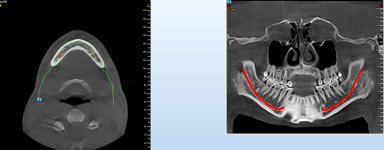

NewTom Implant Planing

Jedná se o plánovací program, který využívá dat získaných při vyšetření pomocí přístroje New Tom. Tento program umožňuje tříprostorovou počítačovou simulaci při plánování pozic implantátů.

Součástí programu je i databáze, ve které mohou být uloženy všechny typy implantátů od všech výrobců, včetně jejich délek, průměrů i tvarů.

Lékař si vytvoří všechny typy zobrazení potřebných pro naplánování – tedy 2D snímky (panoramatický), příčné řezy i 3D model.

Vidí zde i důležité anatomické útvary – čelistní dutinu, průběh nervu atd. Po proměření množství kosti – šířky i výšky vybere z databáze vhodný typ implantátu a umístí ho do požadované lokality.

Ihned vidí jeho pozici ve všech 3 rovinách a na všech snímcích i 3D modelu. Může upravovat podle potřeby jeho pozici, sklon atd.

Všechny vybrané a správně umístěné simulované implantáty se ukládají do „počítačové karty“ pacienta s jejich pozicí, délkou, průměrem, typem i sklonem.

Lékař i pacient tedy ještě před vlastní operací vidí, jak by mělo ošetření probíhat a vypadat.